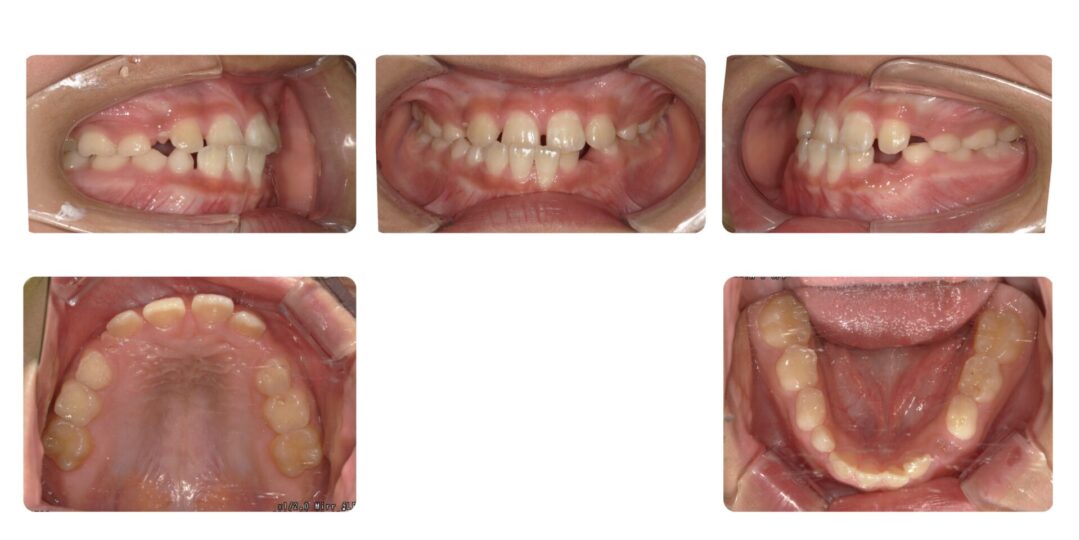

矯正治療前

反対咬合、正中離開が気になる

初診時9歳

第一期治療 上顎拡大床

1年7か月